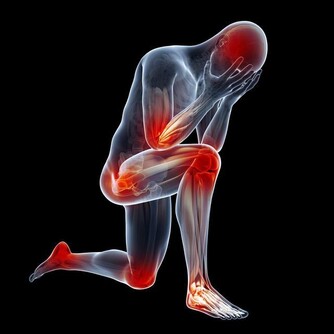

四、胯骨疼痛,可能是薦髂關節功能失調

骶髂關節位於薦骨和髂骨之間,使骨盆保持穩定。當骶髂關節出現問題時,也可能導致胯骨疼痛的發生。骶髂關節功能失調主要與姿勢不良、勞損、產後骨盆鬆弛等因素有關。

長期維持不良的姿勢是導致骶髂關節問題的常見原因。例如久坐或長時間駕駛時,腰薦部容易處於前凸的姿勢,薦髂關節承受較大的壓力,而久站或高跟鞋也增加薦髂關節的負擔。這些都可能導致骶髂關節不穩定、錯位,造成骨盆周圍肌肉收縮,進而感到胯部疼痛。

重複的扭轉、擠壓、搬重物等勞損也可導致骶髂關節受損。這類動作帶給薦髂關節周圍韌帶和肌肉反覆疼痛,長期下來,關節功能逐漸失調。患者常在翻身、改變姿勢時感到胯部和薦骨疼痛。

當骶髂關節發生細微挫傷或錯位時,周圍肌肉會出現保護性痙攣,這也可能導致胯骨局部疼痛。雖然痙攣是身體對骶髂關節損傷的一種恢復反應,但也可能加劇胯骨的不適感。嚴重時,也可能壓迫到骶髂關節附近的薦神經,產生放射痛。

若骶髂關節受損導致的胯骨疼痛持續存在,不僅影響生活,也容易誘發腰薦部肌肉間的紊亂。這進一步加重骶髂關節的負擔,形成惡性循環。